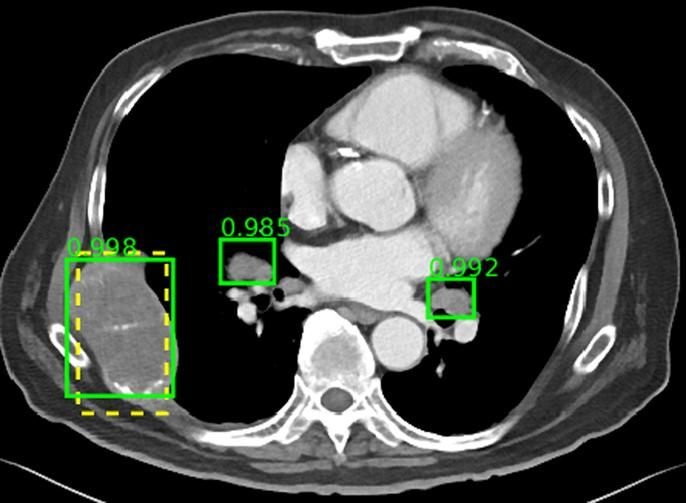

Aunque el grado de conocimiento acerca de la IA en la comunidad radiológica argentina es moderado, encontramos un alto interés y expectativas, y un bajo nivel de miedo o rechazo. Las sociedades radiológicas argentinas deberían desarrollar cursos de formación en IA. Rev Argent Radiol. 2024